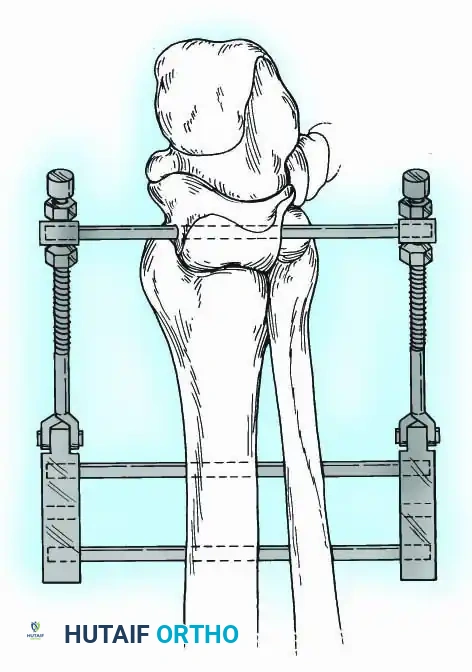

Historically pioneered by Charnley, external compression arthrodesis utilizes pins placed through the distal tibia and the body of the talus. Because Charnley's original uniplanar device lacked rotatory stability, Calandruccio designed a triangular frame to control motion in all three planes while applying massive compression.

Modern iterations, such as the Calandruccio II compression device, offer greater latitude in pin placement to avoid compromised skin. Ring or circular external fixators (Ilizarov, Taylor Spatial Frame) are the gold standard for salvage situations, including active infection, massive bone loss, or failed TAA, as they allow for simultaneous compression, deformity correction, and early weight-bearing.